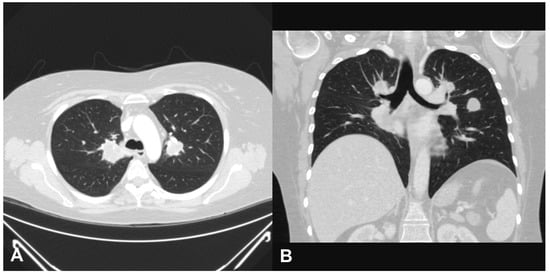

2. Case Report